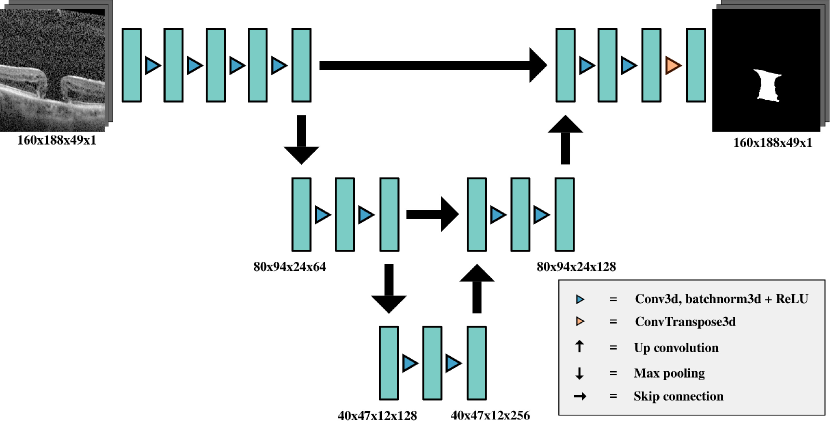

U-Net takes as input a 2D image and outputs a set of probabilities. Each entry in the output is the probability of each part of the image being a part of the segmented region. It is a U-shaped CNN architecture, consisting of a contracting path and an expansive path. The contracting path consists of 2D convolutions, ReLU activations and 2D max pooling at each level. The expansive path’s levels use skip connections to their contracting path equivalent, along with up convolutions and ReLU activations. Skip connections allow for high-resolution information to be captured by the model while the contracting/expansive paths capture the abstract shape of the segmentation. The 3D U-Net architecture [13] is a version of U-Net designed for use with 3D images which uses 3D convolutions, up convolutions and max pooling layers. This allows for improved segmentation of 3D images as the context from multiple slices are used to decide whether an individual voxel is an object or not.

A diagram of model is shown in Figure 1. Our experiments showed that using three levels for this model resulted in the best performance. A scaled-down input image of yielded the best results for models and . The output is of the same dimensions as the input. is similar to except that residual blocks have been added to each level. is a residual 3D U-Net architecture which takes nine slices of the OCT image as input and outputs a 2D probability map as output, representing the segmentation of a single slice of the OCT image. For , the slice which we want to segment, along with 4 slices on either side is input to the model, which is a image. For slices near the boundaries, we use mirroring to handle slices which are outside of the image. It outputs a set of probabilities, corresponding to one slice of the 3D OCT. , therefore, requires 49 iterations to segment a whole 3D OCT image in our dataset. Model has the most parameters of the models tested, with having the fewest parameters.